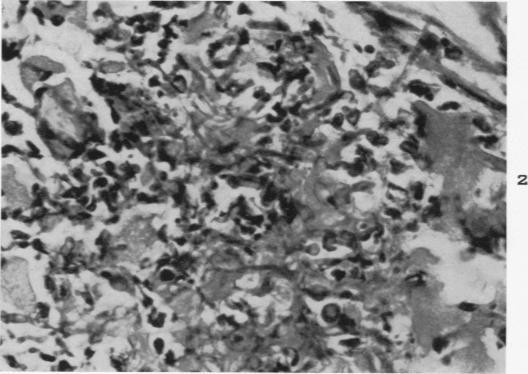

Experimental moniliasis in mice.

Am J Pathol. 1955 Sep-Oct;31(5):859-73.